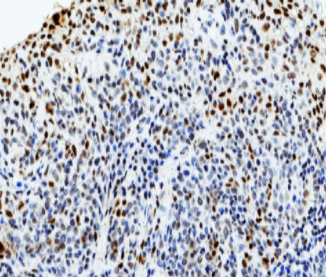

p21抗体是一种特异性识别细胞周期依赖性激酶抑制蛋白(p21/WAF1/CIP1)的免疫检测工具。作为p53信号通路的关键下游效应分子,该蛋白通过结合并抑制cyclin-CDK2/CDK1复合物活性,在G1期检查点调控细胞周期进程,同时能与增殖细胞核抗原(PCNA)相互作用参与DNA损伤修复。正常细胞通常呈现明显的核阳性表达模式,而在胃癌、非小细胞肺癌和甲状腺癌等多种恶性肿瘤中,p21表达缺失与患者不良预后显著相关。该抗体不仅可用于评估p53通路功能状态,其异常表达模式还为肿瘤恶性程度评估提供重要参考依据。

阳性部位:

细胞核